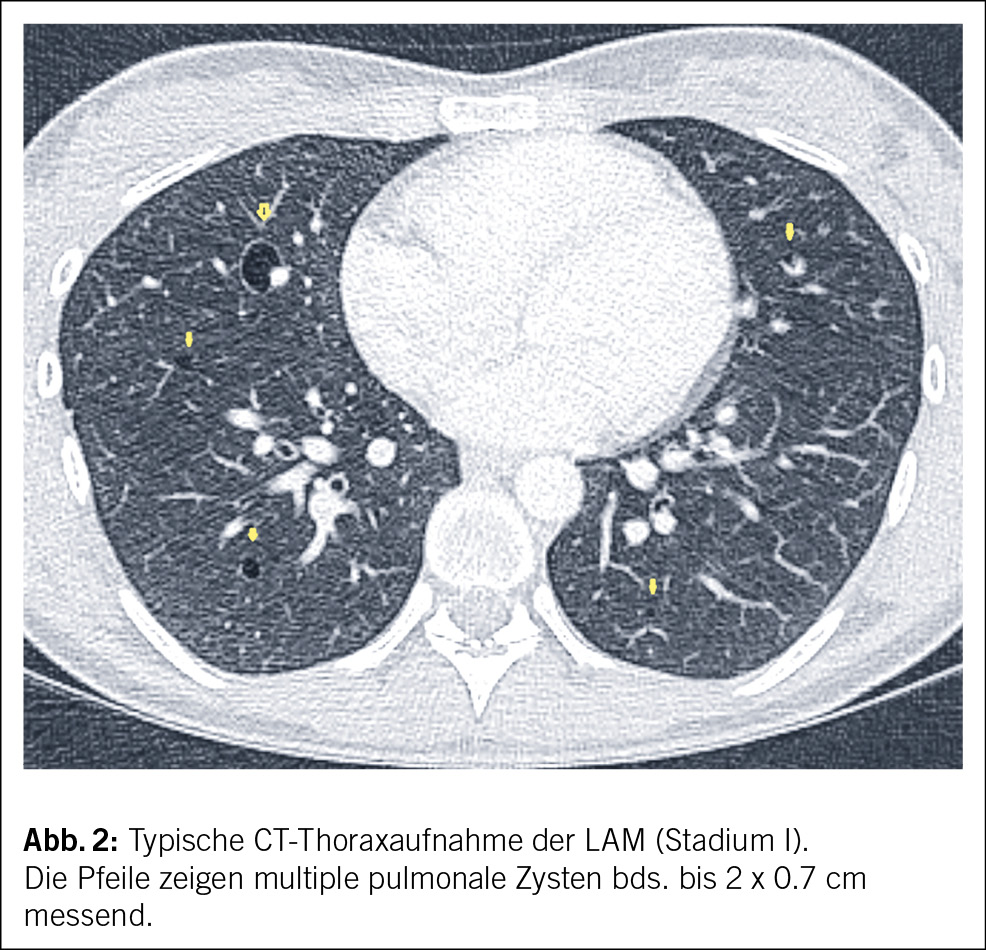

Nach Abwägung der Vor- und Nachteile wurde beschlossen, eine Nierenteilresektion vorzunehmen. Im Rahmen der präoperativen Raumforderungsabklärung mittels thorakaler Computertomographie (CT) wurden einzelne bilaterale, dünnwandige und relativ gleichmässig verteilte Lungenzysten festgestellt ohne weitere Auffälligkeiten (Abb. 2). Ergänzend wurde eine Lungenfunktionstestung durchgeführt, die sich im Normbereich befand.

Wichtige Differenzialdiagnosen bei bilateralen pulmonalen Zysten sind die Langerhans-Zell-Histiozytose (LCH), die lymphoide interstitielle Pneumonie (LIP) und das Birt-Hogg-Dubé-Syndrom (16) (Tab. 2). Bei der vor allem bei Raucherinnen auftretenden LCH sind die Zysten in der Computertomographie heterogen, meist in den oberen Lungenlappen lokalisiert und oft bizarr konfiguriert. Im Gegensatz dazu sind bei der LAM die Zysten rund, haben dünne Wände von 1–2 cm und sind gleichmässig über das gesunde Lungengewebe verteilt. Symptomatische Patientinnen weisen normalerweise eine höhere Anzahl an Zysten auf als asymptomatische (13, 17). Bei der LIP, die vor allem bei Personen mit rheumatologischen Erkrankungen, Kollagenosen und HIV-Infektion auftritt, sind die Zysten typischerweise in den unteren Lungenlappen betont (17, 18). Beim Birt-Hogg-Dubé-Syndrom könnten kutane Läsionen wie Fibrofollikulome oder Trichodiscome sowie eine familiäre Anamnese dieser Erkrankung bedeutsam sein (6, 19).